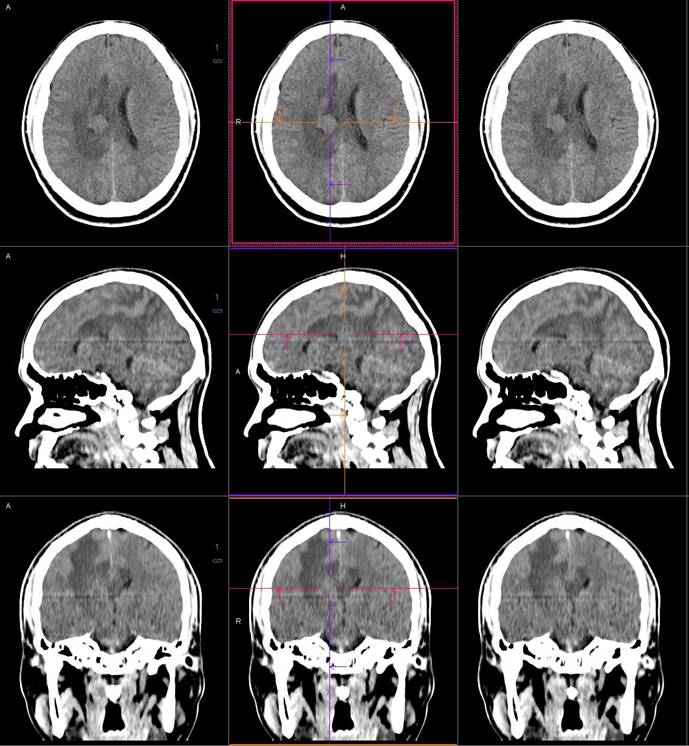

PET/CT影像圖

圖1

圖2

圖3

圖4

PET/CT檢查

影像診斷: 右側(cè)側(cè)腦室旁腦實質(zhì)內(nèi)結節(jié),代謝異常增高(SUVmax 12.13),伴瘤周水腫。

CT鑒別診斷

CT是腦腫瘤的常用檢查方法,CT平掃及增強通過腫瘤的形態(tài)、密度及血供情況等對腦膜瘤的診斷和鑒別診斷有一定的價值。腦膜瘤為腦外腫瘤,但瘤周腦實質(zhì)水腫的出現(xiàn)率也較高,國外報道約60%。本例非典型腦膜瘤可見顯著的瘤周水腫。導致瘤周水腫的機制仍不明確,可能由多種因素參與、共同影響、相互制約所引起的一種血管源性水腫,腫瘤壓迫鄰近引流靜脈容易產(chǎn)生水腫,也有學者認為與腫瘤的血管內(nèi)皮生長因子、水通道蛋白-4高表達等因素有關。